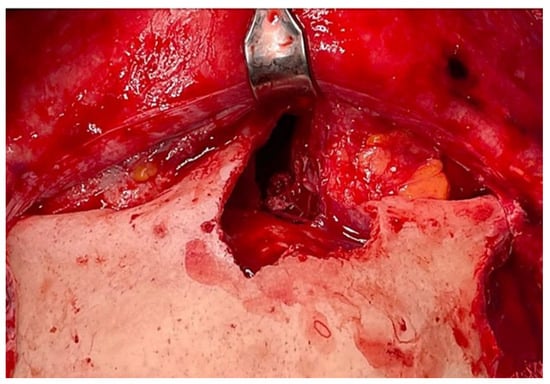

Figure 1.

(A) Preoperative MRI (Time Of Flight TOF sequence in axial view; black asterisk) and CT-scan (B) (axial view; white asterisk) (C) (coronal view; white asterisk), (D) (sagittal view; white asterisk) showing an anterior ethmoidal high vascularized tumor invading the right nasal bone and the medial wall of the right orbit. R = right, P = posterior.